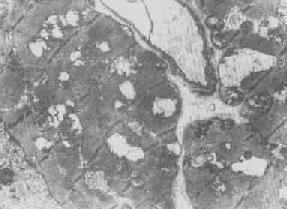

在由各种原因引起的细胞变性和坏死过程中,粗面内质网的池一般出现扩张,较轻的和局限性的扩张只有在电镜下才能窥见,重度扩张时则在光学显微镜下可表现为空泡形成,电镜下有时可见其中含有中等电子密度的絮状物。在较强的扩张时,粗面内质网同时互相离散,膜上的颗粒呈不同程度的脱失。进而内质网本身可断裂成大小不等的片段和大小泡(图1-6)。这些改变大多见于细胞水肿时,故病变不仅见于内质网,也同时累及Golgi器、线粒体和胞浆基质,有时甚至还累及溶解体。

图1-6肝细胞粗面内质网扩张